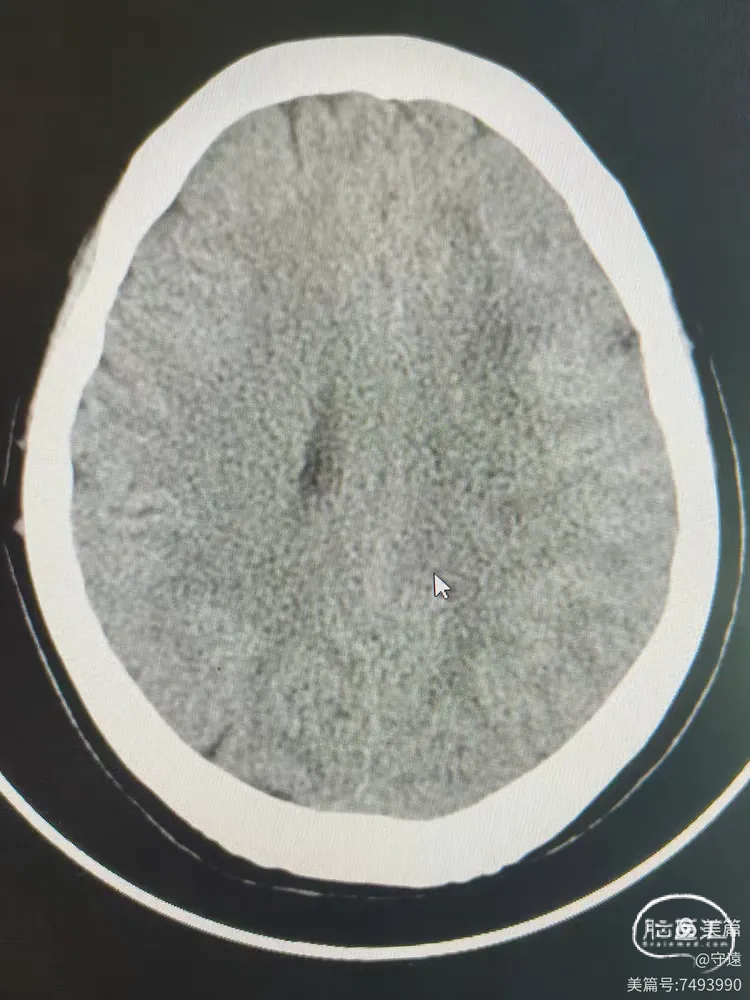

术后18小时复查CT左侧略高影,考虑造影剂滞留,水肿不明显。